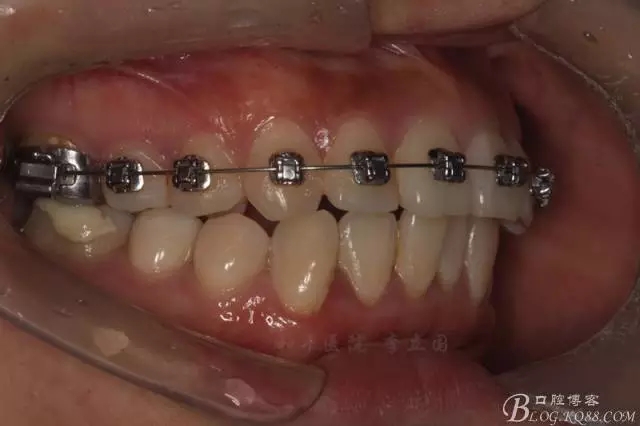

該病例主要為17、27頰側(cè)位同時伴有伸長,當然種植支抗可以解決,但還有簡單實用的辦法嗎?如圖,在橫腭桿遠中延伸出牽引鉤,位置盡量遠離合平面,7粘舌側(cè)扣,牽引力的方向為壓低及舌向,下圖為兩個月的效果,17已到位,27還未到位。